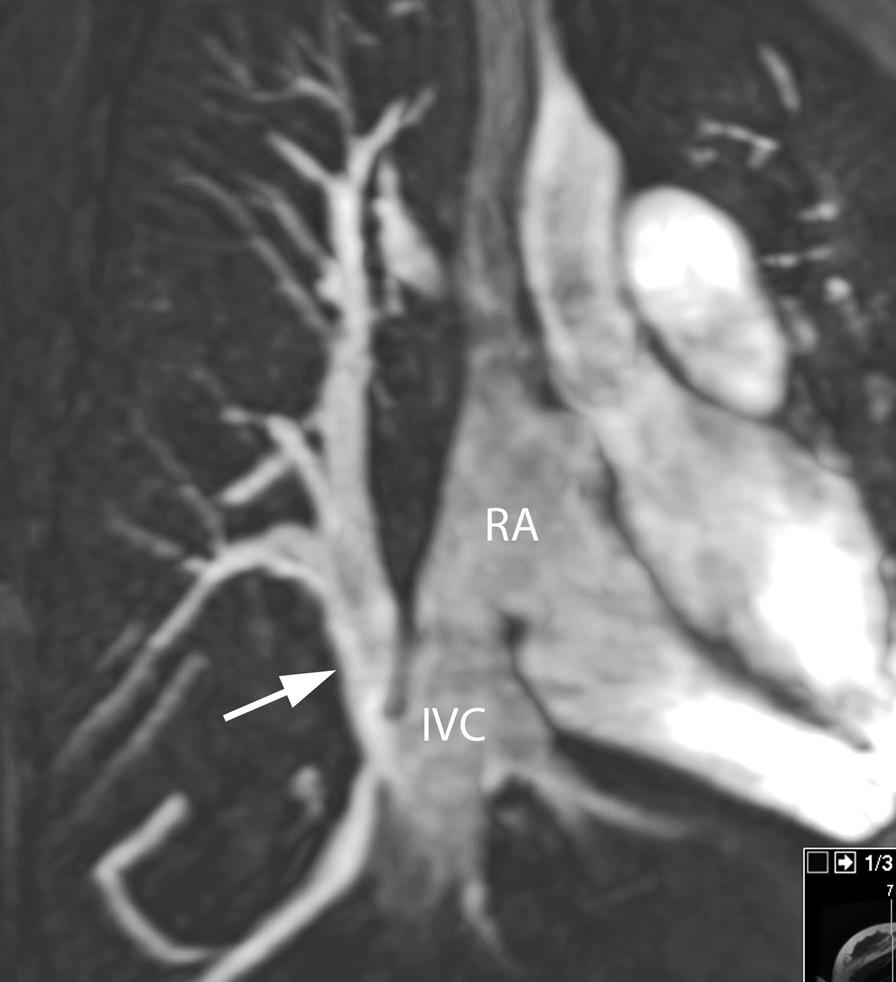

Cardiovascular magnetic resonance (CMR) has been utilized in the management and care of pediatric patients for nearly 40 years. It has evolved to become an invaluable tool in the assessment of the littlest of hearts for diagnosis, pre-interventional management and follow-up care. Although mentioned in a number of consensus and guidelines documents, an up-to-date, large, stand-alone guidance work for the use of CMR in pediatric congenital 36 and acquired 35 heart disease endorsed by numerous Societies involved in the care of these children is lacking. This guidelines document outlines the use of CMR in this patient population for a significant number of heart lesions in this age group and although admittedly, is not an exhaustive treatment, it does deal with an expansive list of many common clinical issues encountered in daily practice.

心血管磁共振(CMR)在儿科患者的管理和护理中已经应用了近 40 年。它已经发展成为评估最小的心脏的宝贵工具,用于诊断、介入前管理和随访。尽管在许多共识和指南文件中提到,但在儿科先天性心脏病和后天性心脏病领域,目前还缺乏一份由众多参与儿童护理的学会共同认可的、最新的、独立的、针对 CMR 使用的大型指南。本指南文件概述了 CMR 在该年龄段的许多心脏病变中的应用,尽管不能说是详尽的治疗方法,但它确实涉及了在日常实践中经常遇到的许多常见临床问题的广泛列表。